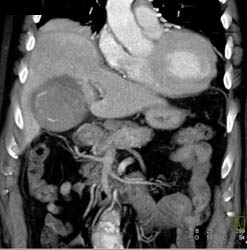

Acute Cholecystitis